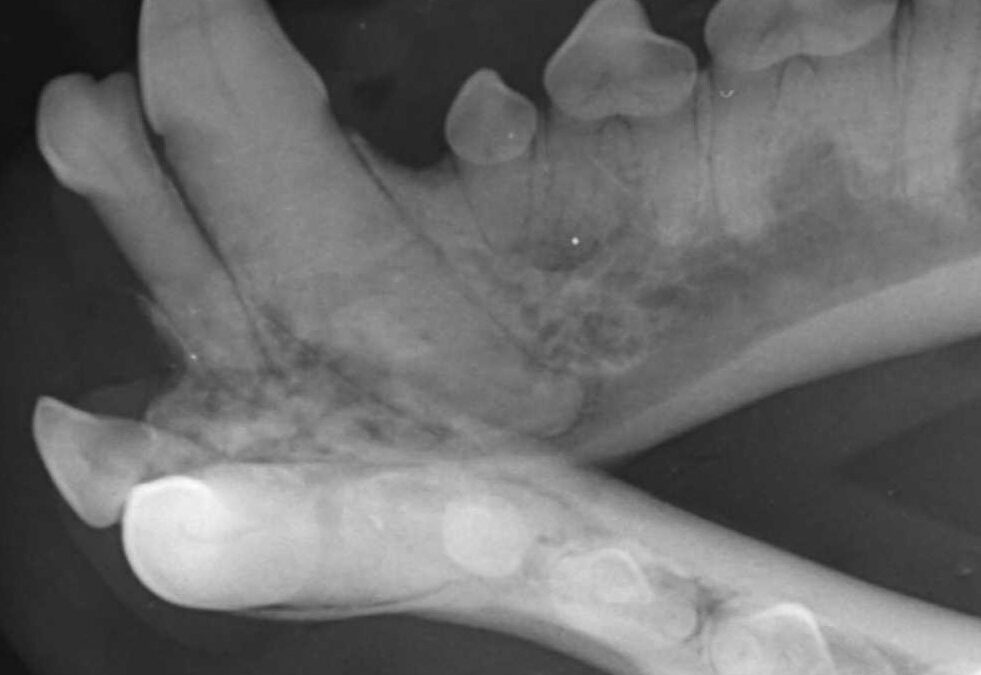

Bonny-Hills-Vet—Dental